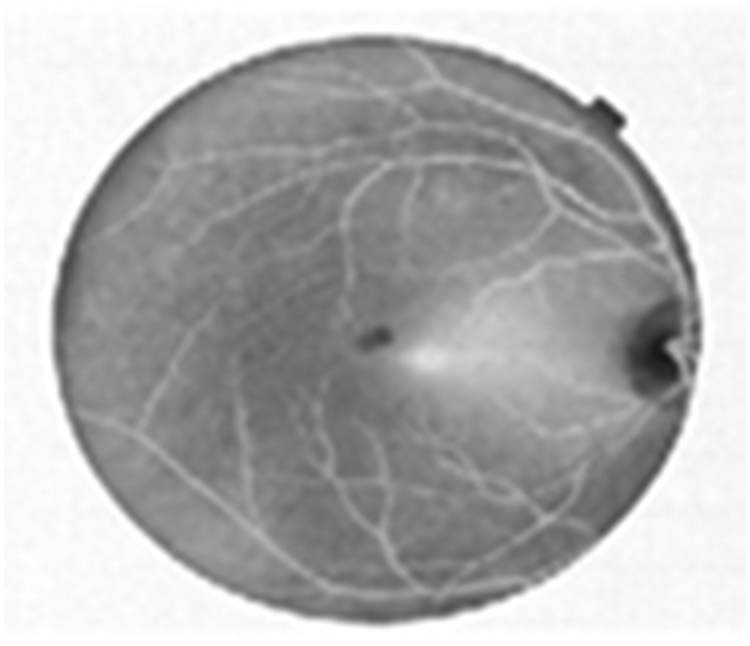

The retinal images were taken individually from all the databases and were subjected to contrast enhancement using CLAHE. Input image is shown in Figure 2. Blood vessel enhanced image is shown in Figure 3.

Blood vessel enhanced image using CLAHE.